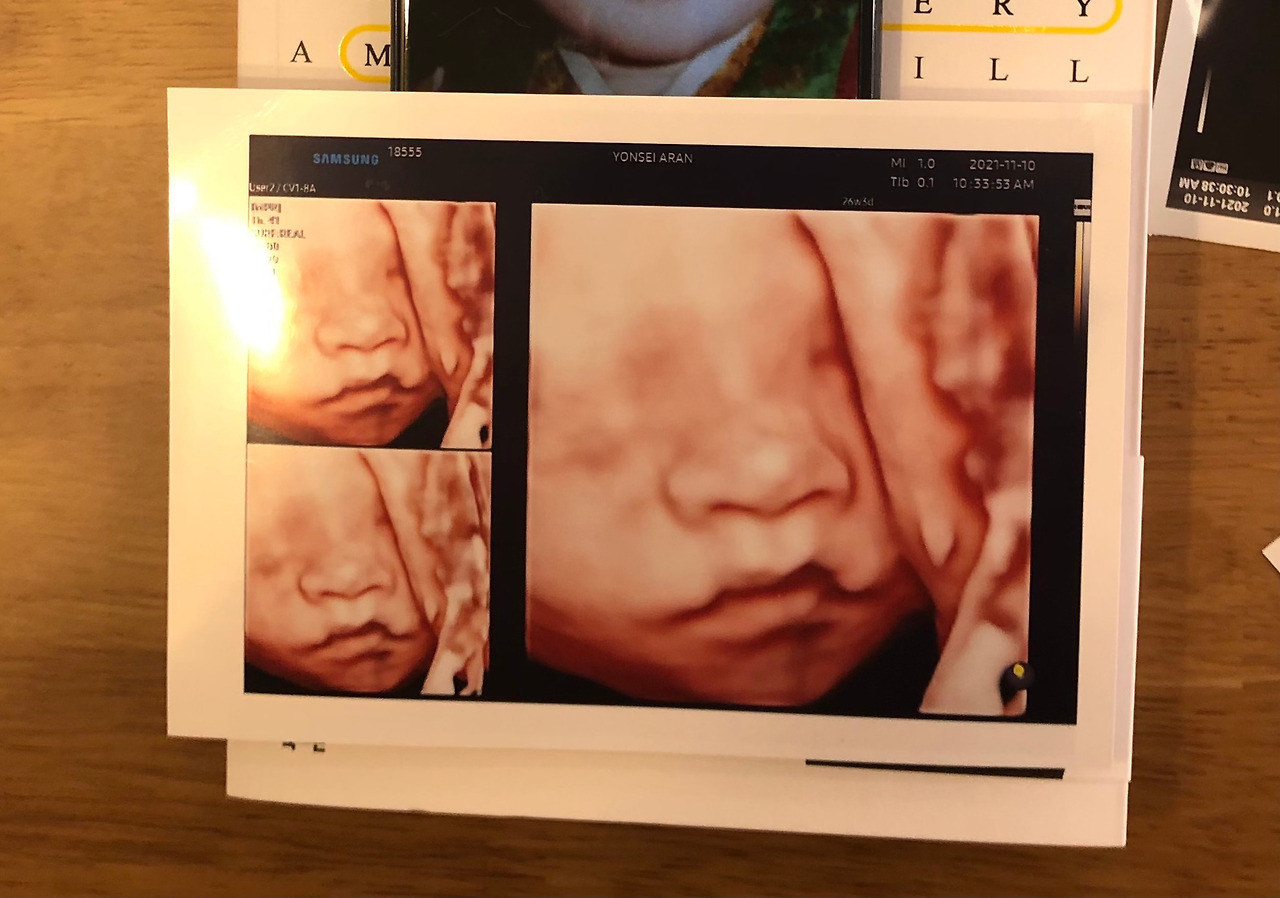

입체 초음파

그날이다. 임신 26주 차가 되면서 '3D 입체 초음파'라는 것을 하는 날이다. 입체 초음파란? 태아 외관에 입체영상을 제공하여, 얼굴 모습과 더불어 외형적인 부분을 좀 더 사실적으로 확인이 가능한 검사이다. 손가락, 발가락, 구순개열 등 확인이 가능한데, 솔직하게 얘기하면 돈을 내면서까지 아이의 얼굴을 확인해보고 싶은 엄마의 바람이 조금은 담겨 있다. 부모를 위한 추억이라는 말이 있을 정도니까 말이다. 결국, 우리도 검사를 받았다. 현주씨 혼자 병원에 올라갔고, 한 시간 동안 근처 카페에서 여유 있게 커피 한 잔 마시며 기다렸다. 그리고 한 통의 전화가 오며, 다소 텐션이 올라간 목소리가 들렸다. 망했어. 아빠 코 닮았어 순간 멈칫했다. 예언들이 떠올랐고, 카페 안에 있던 작은 거울에 비친 내 모습을 바라보게 되었다. "아뿔싸..."

임창정의 '날 닮은 너'라는 노래가 떠올랐다. 내용은 다르지만 왠지 구슬픈 노래가 더 와닿는 거 같다. 애써 침착하게 네이버 앱을 켜고, 검색을 했다. '아빠를 닮은 아이'가 궁금해졌다. 많은 뉴스와 논문, 글 등 정보를 취득하기 시작했다. 오!! 좋은 내용들만 눈에 띄기 시작했다. '신생아가 아빠를 닮을수록, 아빠와 유대감이 좋을수록 1살이 되었을 때 더 건강하다는 연구결과'라는 내용이었다. 뉴욕 주립 빙엄턴대학교의 연구팀은 715가정의 아이 건강상태를 분석했는데 아빠를 닮았을 경우, 천식, 병원진료/방문횟수, 응급실 방문횟수, 가장 오래 병원 머문 기간 등이 낮은 것으로 밝혀졌다는 내용이었다. 아빠들은 '내 아이'라는 책임감을 갖게 된다고 한다. 아빠를 닮을수록 한 달기준 2.5일 더 육아에 할애하는 시간도 길었다고 한다. 아버지라는 존재가 중요한 역할을 할 수 있다는 말인데 그래서 일까? 애써 아빠를 닮은 나의 '단아'가 왠지 더 소중하게 느껴졌다. 그리고 시간이 얼마 지났을까, 아내는 3D 초음파 사진을 눈앞에 꺼내놨다. 촤르륵 수많은 사진들 속에 유난히 날 닮은 아이가 눈에 띄었다. 주여... 어딘가 날 닮은 코를 가진 아이. 약간은 콧대가 낮아 보이고, 콧 평수가 조금은 여유 있는 귀여운 아이였다. 입술은 누가 봐도 엄마를 닮은 거 같았다. 그런데 막상 진짜 닮은 단아를 보았을 때 조금은 남다른 기분이 감도는 게 아닌가. "진짜 내 딸이네?!, 진짜 우리 닮았다!"